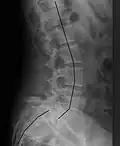

| X-ray of the lateral lumbar spine with a grade III anterolisthesis at the L5-S1 level | |

Spondylolisthesis is graded based upon the degree of slippage of one vertebral body relative to the subsequent adjacent vertebral body.[6] Spondylolisthesis is classified as one of the six major etiologies: degenerative, traumatic, dysplastic, isthmic, pathologic, or post-surgical.[7] Spondylolisthesis most commonly occurs in the lumbar spine, primarily at the L5-S1 level, with the L5 vertebral body anteriorly translating over the S1 vertebral body.[7]

- Grade III: 50–75%